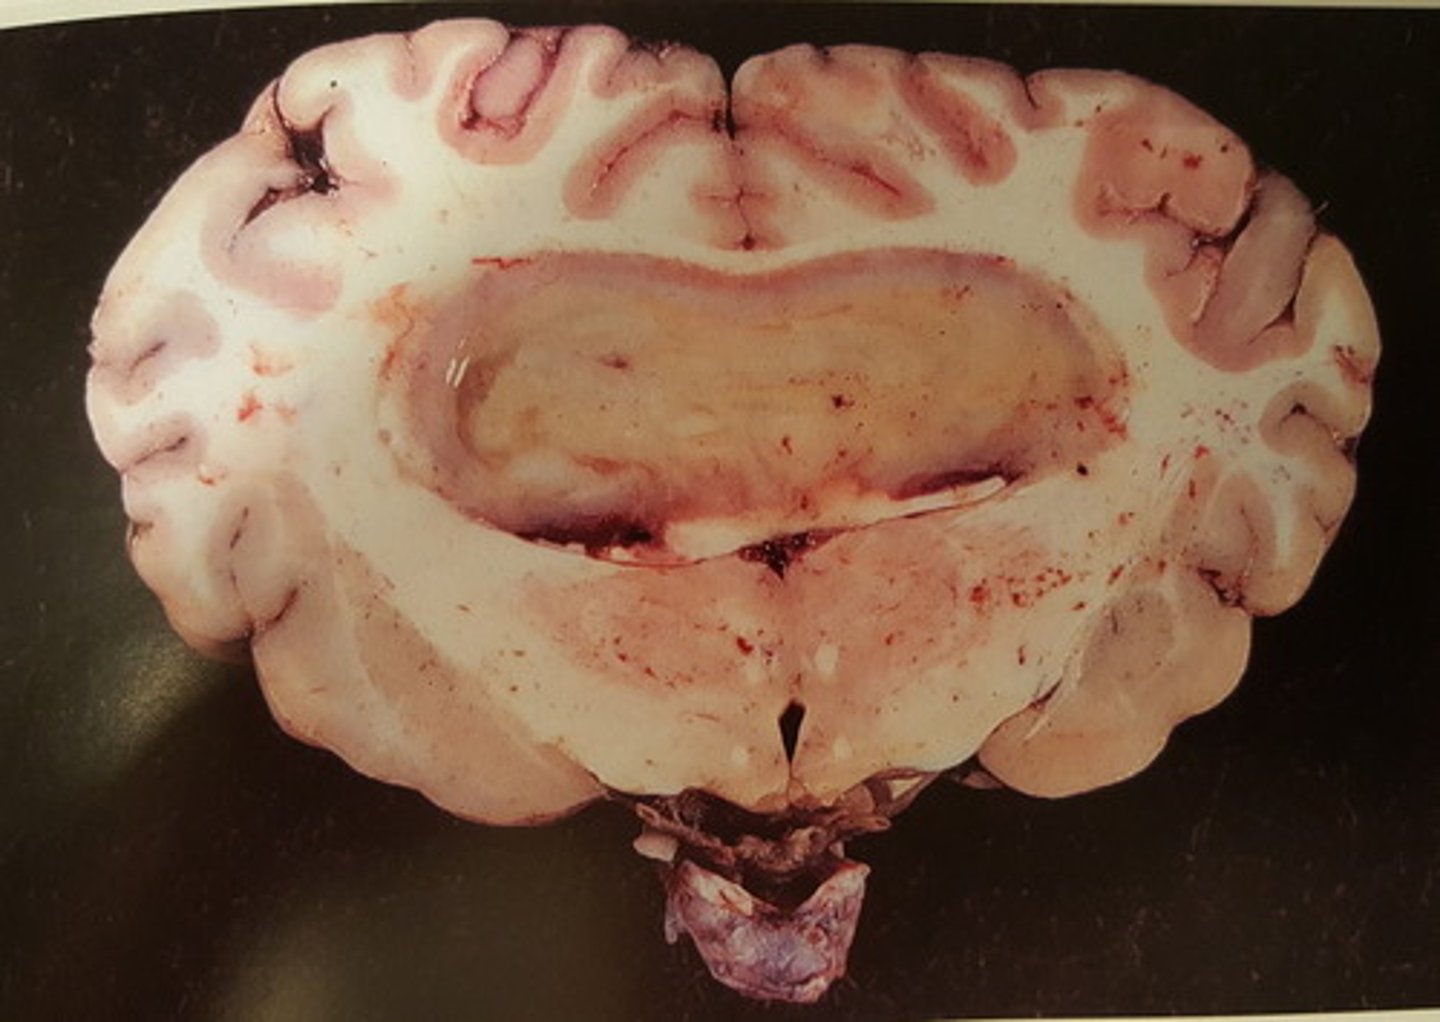

kronisk diffus pyocephali med dilation af ventrikelsystemet

Hjerne fra okse. Patoanatomisk diagnose?